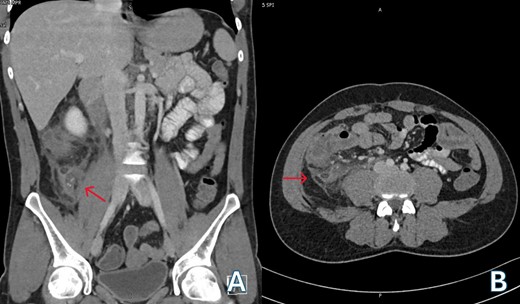

A 24-year-old Bangladeshi male presented to our emergency department with a 4-day history of right iliac fossa pain and fever. The patient denied experiencing diarrhea, vomiting, upper respiratory tract infection symptoms, radiation of pain, anorexia, testicular pain, or constipation. On examination, his temperature was 38.7°C, heart rate 108 bpm, blood pressure 116/66 mmHg, respiratory rate 18 breaths per minute, and oxygen saturation 100% in room air. Abdominal examination revealed localized tenderness and guarding in the right iliac fossa, along with positive rebound tenderness and Rovsing’s sign. Psoas sign and obturator sign were also elicited. Differential diagnoses included acute appendicitis, among other causes of abdominal pain, such as gastroenteritis, mesenteric lymphadenitis, incarcerated inguinal hernia, acute diverticulitis (less common in younger individuals), and pelvic inflammatory disease (less common in males). Investigations comprised laboratory tests, revealing elevated white blood cell count (14.1 × 103/μl) and C-reactive protein (CRP) levels (228.2 mg/L), and imaging via Computed Tomography (CT) abdomen and pelvis, which confirmed an acutely inflamed retrocecal appendix with a suspicious sealed perforation and an abscess cavity behind the cecum (Fig. 1). Blood cultures were collected in two anaerobic and two aerobic bottles at the time of admission. These bottles were placed in a BacT/Alert system (Becton Dickinson, NJ) for incubation. On Day 3, tests from both anaerobic blood culture bottles came back positive, at 52 and 59.5 hours, respectively, and gram stain analysis revealed the presence of Gram-negative bacteria (Fig. 2B) when observed under a microscope. Specimens were then grown on common blood agar plates under anaerobic conditions at 35°C. On Day 5 after presentation, moist and gray-white colonies were found (Fig. 2A). These were rapidly identified as O. splanchnicus using matrix-assisted laser desorption/ionization-time of flight mass spectrometry (MALDI-TOF MS) Biotyper (Library BDAL-11897-4274 Version 12, Bruker Daltonics, Bremen, Germany) on the same day. Treatment involved laparoscopic appendectomy (Fig. 3) and subsequent administration of intravenous amoxicillin–clavulanate 1.2 g three times a day for 10 days. The patient responded well to treatment, with normalization of laboratory values (discharge CRP: 67.7mg/L) and resolution of fever. Blood culture repeated after 72 h of intravenous antibiotics was negative.

(A) Venous phase computed tomography (CT) of abdomen showing dilated appendix with peri appendicular fat stranding and inflammation (red arrow); (B) Axial computed tomography (CT) of abdomen showing retrocecal appendix with severe inflammation involving up to the retroperitoneal musculature (red arrow).